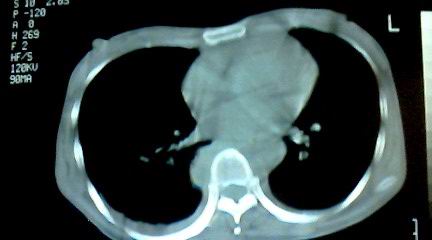

标题: CT25218:请教!胸部CT,胸8椎体骨质破坏,伴周围软组织肿。 [打印本页]

标题: CT25218:请教!胸部CT,胸8椎体骨质破坏,伴周围软组织肿。

患者,女41岁,肢体乏力。

两肺上叶继发性肺结核;胸椎结核并椎旁寒性脓肿形成。

胸椎结核并椎旁寒性脓肿形成。